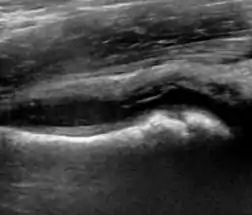

During childhood, ultrasound is a quick method to assess hip pain and quite often may be used to avoid use of irradiating techniques, such as radiography or CT. Ultrasound allows evaluation of joint effusion, synovial thickening and neovascularity, the bone/cartilage contour, and the femoral head-neck alignment. Although sonography is extremely sensitive in detecting increased synovial fluid, it is nonspecific and cannot be used with accuracy to determine the type of fluid. Transient synovitis of the hip, despite being the most frequent cause of pain in children between 3 and 10 years, remains a diagnosis of exclusion. It usually shows anechoic fluid, but echogenic fluid can also be found. The effusion is considered pathologic when it is measured at >2 mm in thickness. The differential diagnosis is wide, including osteomyelitis, septic arthritis, primary or metastatic lesions, LCPD, and SCFE. Discrimination from septic arthritis is challenging, often requiring joint aspiration. In septic arthritis, US is able to demonstrate a hip joint effusion, synovial thickening, and cartilage damage, although the appearances are nonspecific.[1]

Figure 12:

Normal ultrasound appearance of the femoral head-neck junction.

Normal ultrasound appearance of the femoral head-neck junction. Joint effusion in transient synovitis of the hip.

Joint effusion in transient synovitis of the hip. Flattening of the femoral head in a patient with Perthes disease.

Flattening of the femoral head in a patient with Perthes disease. Step in the femoral head-neck junction in a patient with SCFE.

Step in the femoral head-neck junction in a patient with SCFE.

In adults, the most common application for US is to detect tendon or muscle injuries, effusion or synovitis within the hip joint or its adjacent bursae. Joint effusions may be due to many intra-articular processes and this may need another imaging technique to achieve a specific diagnosis.[1]